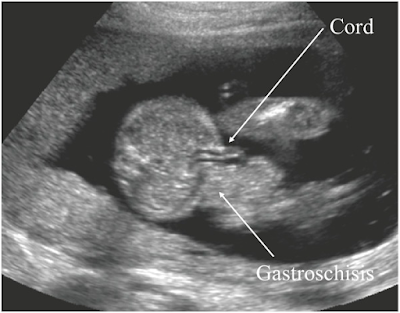

2. Gastroschisis

- Most often right-sided

- Full thickness paraumbilical defect of the abdominal wall